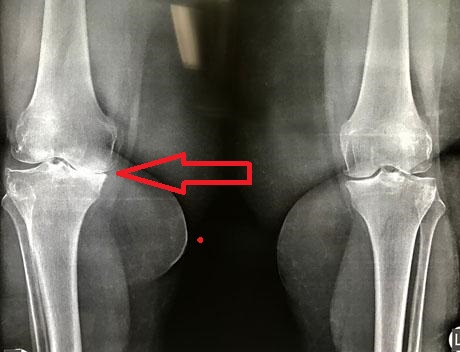

Προεγχειρητικός ακτινολογικός έλεγχος σε όρθια θέση της ασθενούς. Η παραμόρφωση βλαισότητας στο αριστερό γόνατο ξεπερνά τις 15 μοίρες με φόρτιση των σκελών.

Μέτρηση της παραμόρφωσης της βλαισότητας κατά τον προεγχειρητικό ηλεκτρονικό σχεδιασμό της εξατομικευμένης αρθροπλαστικής γόνατος PSI. Δίχως φόρτιση του αριστερού σκέλους ξεπερνά τις 10 μοίρες.